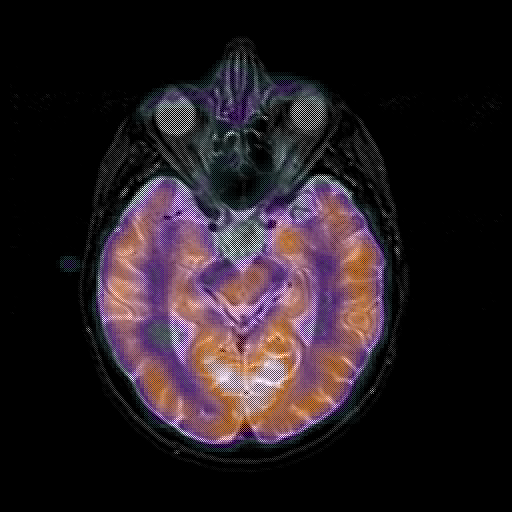

overlay 1: Slice 23

Slice 23

MRCBFCBF with

T1PDT2T1PDT2